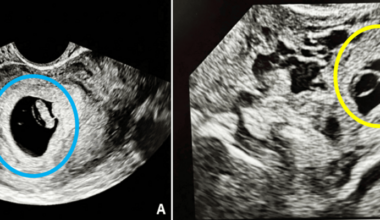

HHealth Read More Laparoscopic Management of Spontaneous Heterotopic Pregnancy With Preservation of Intrauterine PregnancyApril 16, 2026 Specialty Please choose I’m not a medical professional. Allergy and Immunology Anatomy Anesthesiology Biostatistics Cardiac/Thoracic/Vascular Surgery Cardiology Critical…